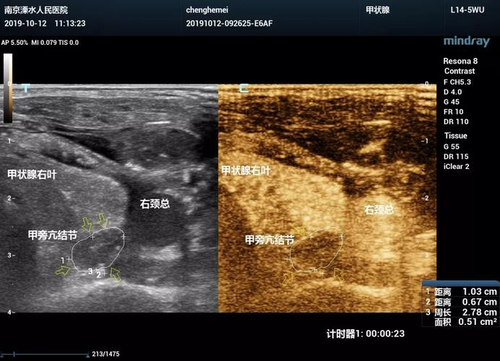

1、脏器声学造影是一种专门用于检查人的脏器健康状况的手段,可以确诊出人的肝肾,以及心脏有没有病灶,也可以确诊出肿瘤的严重程度和大小,所以一些疑似患有脏器疾病的人,医生会让其采用脏器声学造影的方式来做确诊。

2、脏器声学造影这项检查要比普通的x光片,CT这些检查方法更加精准,更加方便,检查的器官部位也更加全面,现在已经被,公立正规医院普遍使用。